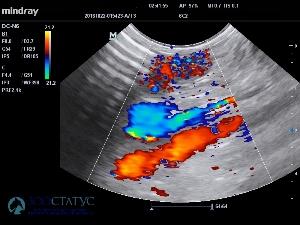

УЗИ брюшной полости может выявить инвагинацию, нарушение моторики кишечника, однако УЗИ не является экспертным методом для диагностики кишечной непроходимости.